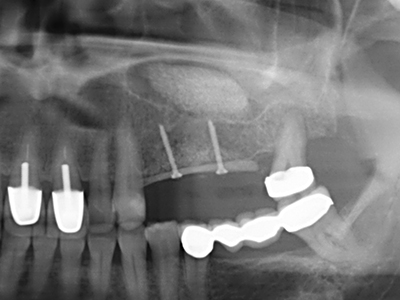

Fig. 11: The postoperative panoramic image shows the vertical augmentation and sinus floor elevation.

Fig. 12: After six months of healing, the alveolar ridge is vital and sufficiently dimensioned in all planes.